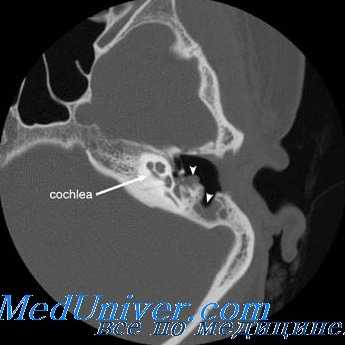

При абсцессе мозжечка инфекция распространяется преимущественно из пораженного лабиринта (при хронических гнойных средних отитах) или из тромбированной поперечной (сигмовидной пазухи). При гнойном лабиринте инфекция может проникнуть в мозжечок после разрушения костного лабиринта (чаще всего задний полукружный канал) по перилабиринтным клеткам (контактный путь) или по преформированным путям (водопроводы преддверия и улитки и внутренний слуховой проход).